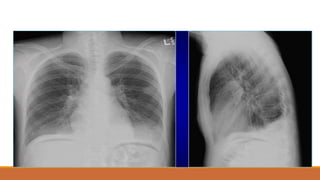

TDMP lượng nhiều

TDMP ÁP LỰC, ĐẨY TRUNG THẤT VỀ PHÍA ĐỐIDIỆN

TDMP THỂ HOÀNH

PHIM ĐỨNG

◦ KHÔNG CÓ ĐƯỜNG CONG DAMOISEAU

◦ BÊN (T): ĐÁY PHỔI CAO, TĂNG KC BÓNG HƠI DẠ DÀY-ĐÁY PHỔI >

1,5CM

◦ BÊN (P): ĐÁY PHỔI (P) CAO BẤT THƯỜNG VỚI ĐỈNH LỆCH RA

NGOÀI ĐƯỜNG TRUNG ĐÒN